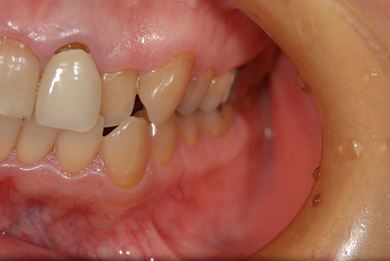

セラミック治療+ラミネートベニア治療

| 主訴 | 虫歯を白い詰め物で治療したい。全体的に歯の色が気になるので、ホワイトニングをしたい。ホワイトニングの効果がなければ、セラミック治療を受けたい。 | ||||||||||||||||||||||||||||||||

| 治療方針 | セラミック治療にて、審美的回復を行う。 | ||||||||||||||||||||||||||||||||

| 治療内容 | ジルコニアオールセラミッククラウン1本(オールセラミック用土台1本)、オールセラミッククラウン9本(オールセラミック用土台1本)、オールセラミックラミネートベニア11本 | ||||||||||||||||||||||||||||||||